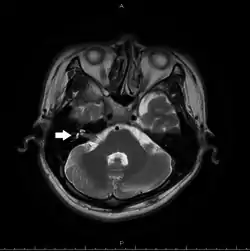

Найчастіше в практиці використовують методи нейровізуалізації — МРТ та КТ[71][72]. Іншим важливим дослідженням є ЕМГ[73]. Аудіометрія та імпедансометрія дозволяють диференціювати порушення VIII та VII нервів та виміряти амплітуду стремінцевого рефлексу[68].

При використанні КТ не можна візуалізувати лицевий нерв, але метод добре візуалізує кісткову тканину. Тому у випадку підозри на травматичне пошкодження лицевого нерва, яке найчастіше виникає у каналі лицевого нерва, використовують саме цей метод.[71] Також він може виявити кальцифікати (наприклад, при гемангіомі нерва) та холестеатому[72].

При використанні МРТ в T2-режимі можна візуалізувати як лицевий нерв, так і інші нервові анатомічні утвори. МРТ дозволяє краще за КТ визначати як над'ядерні, так і ядерні ушкодження (наприклад, інсульти); дозволяє побачити сам нерв у різних його сегментах, в тому числі при виході зі стовбура мозку. При використанні МР-ангіографії можна визначити співвідношення між судинами та нервом, що є важливим в діагностиці геміфаціального спазму[71].

Патологія мосто-мозочкового кута

Ураження корінця лицевого нерва в цій ділянці найчастіше викликається невриномою VIII черепного нерва. Лицевий нерв перебуває дуже близько до цього нерва і цим пояснюється його включення в патологічний процес. Компресія невриномою VIII черепного нерва чи стиснення іншим утвором проявляється в синдром мосто-мозочкового кута (синдром бічної цистерни). Симптомами будуть порушення усіх видів іннервації, які забезпечуються лицевим та присінково-завитковим нервами. При розростанні пухлини чи збільшенні іншого утвору до процесу можуть залучатися V та VI пари черепних нервів, мозочок.[75][89]

Ще одною патологією, яка пов'язана з цим сегментом є геміфаціальний спазм. Це захворювання яке характеризується раптовими неконтрольованими тонічними або тоніко-клонічними судомами, які проявляються у вигляді нападів[90]. Між нападами жодних інших неврологічних симптомів з боку лицевого чи інших нервових утворів немає. Причиною таких судом найчастіше є подразнення корінців нерва судиною в ділянці так званого root entry zone — місця входу корінця, хоча трапляються випадки, коли місце подразнення може локалізуватися на в будь-якій ділянці, починаючи від ядра і закінчуючи шило-соскоподібним отвором, а подразником може виступати не тільки судина, а й кісти, фістули, пухлини[91]. Часом до судом додається невралгія трійчастого нерва[92].